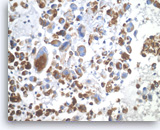

Acinar cell carcinoma,

Pancreas FNA, Cell Block.

The tumor cells are focally positive for chymotrypsin.

40X